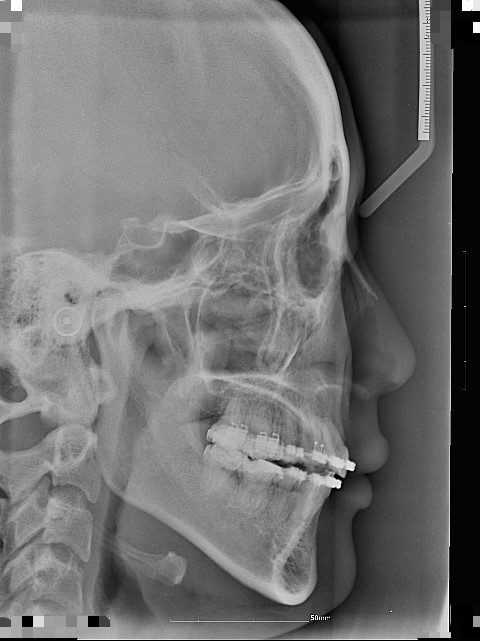

옆모습 입술라인은 교정장치를 제거하면 조금 들어가보일지 모르나 윗입술 아랫입술의 간격은 어차피 같지않겠습니까? 그게 가장걱정입니다. 윗입술이 들어가보이는만큼 아랫입술도 또 브라켓이차지하던 빈자리로 들어가면 윗입술만 나와보이고..현재도 측면사진이나 무표정일땐 윗입술만 툭 인중전체가 다 툭 나와보입니다 ㅠㅠ

1)상악을 더 넣게된다면 하악이 더 들어가서 턱이 나와보여 안된다하시고

이가 맞물리는 위아래 교합만 맞추고 끝을 내면 된다하십니다.하악 치열 어금니들이 안쪽으로 쏠린것은 상악에 맞추는것이므로 굳이 상관없다고 하십니다. 고무줄로 상하악의 치아를 걸어주어 교합맞추고 철사바꾸고 이런식으로 마무리를 6개월을 하면 끝이 난다고 합니다. 그리고 지금의 입술라인 크게 변화없다고 하십니다

2)개선목표는 상하악치아 교합과 상악을 뒤로 2m가량 더 넣고 앞니를 살짝 위로 올려 잇몸을 보이며 웃는 웃음을 개선입니다. 치료과정은 하악교합라인을 맞추고 (치열과,안으로 쏠린 치아들 바로 세우는 등) 고정뒤 상악 어금니가 발치공간을 닫던중 앞으로 약간 쏠린것으로 보셔서 가지런히 놓은뒤 안쪽에서 두번째 어금니를 치열에 맞게 재배치한후 스크류를 박은뒤 여백의 공간을 닫은뒤 앞니를 위로 뒤로 이동시키고 마무리 교합하시는것으로 교정을 마무리 하고자 하십니다. 약 1년 6개월이 걸릴것이라고 하구요. 그리고 지금의 상악하악 입술관계는 그로인해 어느정도 개선가능하시다고 봅니다.

가장불만인 윗입술인중과 아랫입술의 돌출차이입니다 ㅠㅠ